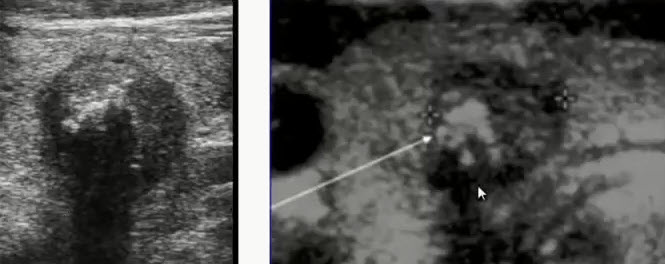

Фотографии опухоли медуллярной аденокарциномы

Раздел: Снимки-откровения